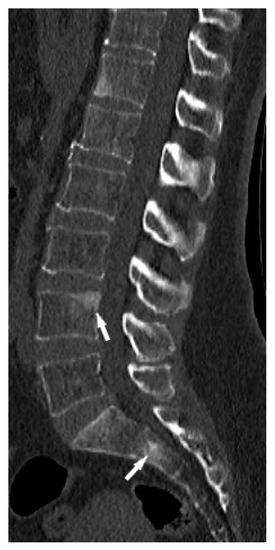

The lumbar spine MRI revealed protrusion of an intervertebral disc with compression on the dural sac and nerve roots, which presumably caused the symptoms. Moreover, the images of lumbar vertebrae and pelvis showed disseminated, small enhancing lesions (Figure 11a,b), which were isointense on T1- and T2-weighted images, hyperintense on TIRM images and revealed restricted water diffusion. The MRI appearance of the lesions was nonspecific. However, the radiologist interpreting the results had access to clinical data so the differential diagnosis took into account both sarcoidosis and metastases.

It was decided to repeat bronchoscopy. Pathological confirmation of sarcoidosis was obtained from a biopsy of the bronchial mucosa (non-necrotizing granulomas and multinucleated giant cells). To exclude other than sarcoidosis changes in the bones and bone marrow, the patient was consulted in hematology and orthopedic medical centers. Iliac bone biopsy revealed multinucleated giant cells and epithelioid granulomas without necrosis. In bone fragment-containing bone marrow, the image was suggestive of sarcoid granulomas as well. Due to confirmation of sarcoidosis with bone and bone marrow involvement and progression of lung disease, prednisone at a dose of 30 mg per day and methotrexate at a dose of 20 mg per week was implemented. As a result of treatment, almost complete regression of lung disease in the control chest CT, and normalization of respiratory parameters, was observed. Normalization of calcium level in 24-h urine test (Table 1), and regression of enlarged lymphatic abdominal nodes were also noted. Control MR imaging showed almost complete regression of intramedullary foci in lumbar vertebrae and complete regression of intramedullary foci in the pelvic bone elements (Figure 11c,d). Therefore, the dose of prednisone was gradually reduced to 10 mg per day and methotrexate to 10 mg per week.

Figure 11. 34-year-old patient. T1-weighted images, contrast enhanced, with fat saturation of the lumbar spine and pelvis. Multiple enhanced bone marrow lesions in the vertebral bodies ((a), white arrow) and in the pelvis at the level of the sacroiliac joints ((b), white arrow). Complete regression of the lesions after the treatment in the vertebral bodies (c) and pelvis (d).